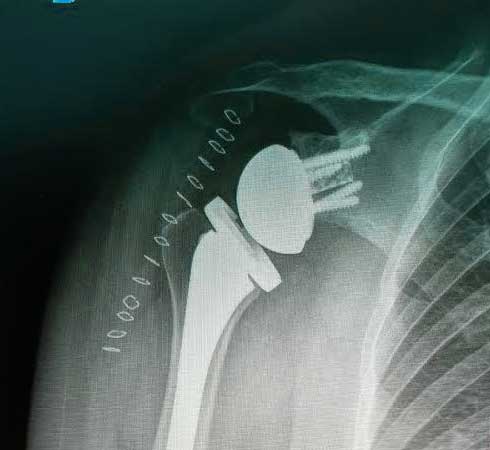

Es la sustitución artificial de la articulación por un implante de metal y polietileno indicada por artrosis, desgaste o lesión masiva del manguito rotador.

La razón más frecuente es aliviar el dolor intenso causado por artrosis, corregir las deformidades angulares en varo, valgo y contractura en flexión en adultos mayores y para adultos jóvenes, está indicada en lesiones crónicas articulares que ocasionan un desgaste acelerado.

La recuperación de la cirugía reemplazo de hombro con una prótesis reversa de hombro o una prótesis anatómica de hombro va muy ligada al estado de la articulación previamente lesionada y al apego que tenga el paciente con la terapia física y así poder ofrecer una recuperación buena, muy buena o excelente.

Radiografía postquirúrgica de prótesis reversa de hombro derecho.